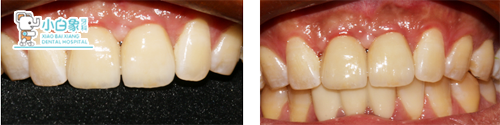

2017年11月24日 11、21戴牙。

2017年12月25日 11、21 修复体复查。